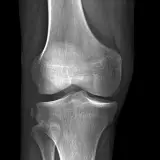

Over 2,100 interactive radiology cases, curated by radiologists for your level of training. Scroll, window, and view cases full screen — just like on PACS. Click linked findings in each writeup to jump straight to them on the image. Cases include sample reports, a focused discussion section, original illustrations, and videos.

Our site includes 3 main courses: Call Preparation, Introduction to Radiology, and Neuro Fellowship.

Call Preparation — our comprehensive curriculum for junior residents preparing for call covering both classic and atypical presentations. Use the call simulator to practice a real call shift — shuffle cases, enter your own preliminary report, and receive constructive AI feedback.

Casos totalmente interativos com as ferramentas que você espera em um PACS — rolagem, ajuste de janela, zoom, movimentação, medidas, ROIs e modo de tela cheia.

Anotações detalhadas destacam os achados principais diretamente nos casos. Clique nos achados vinculados nas descrições dos casos para ir ao local exato no exame.

Aprenda com eficiência com achados de imagem anotados e ilustrações